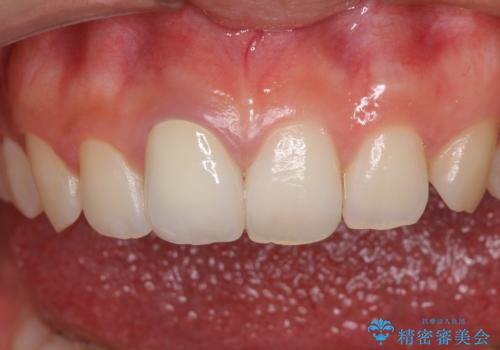

あっという間に気になっていた変色が解決し、早く治療を始めれば良かったとおっしゃっていました。

オーダーメイドタイプのクラウンを選択いただいたので、まるで天然の歯と見間違うほど自然に仕上がり、患者様には大変満足していただきました。